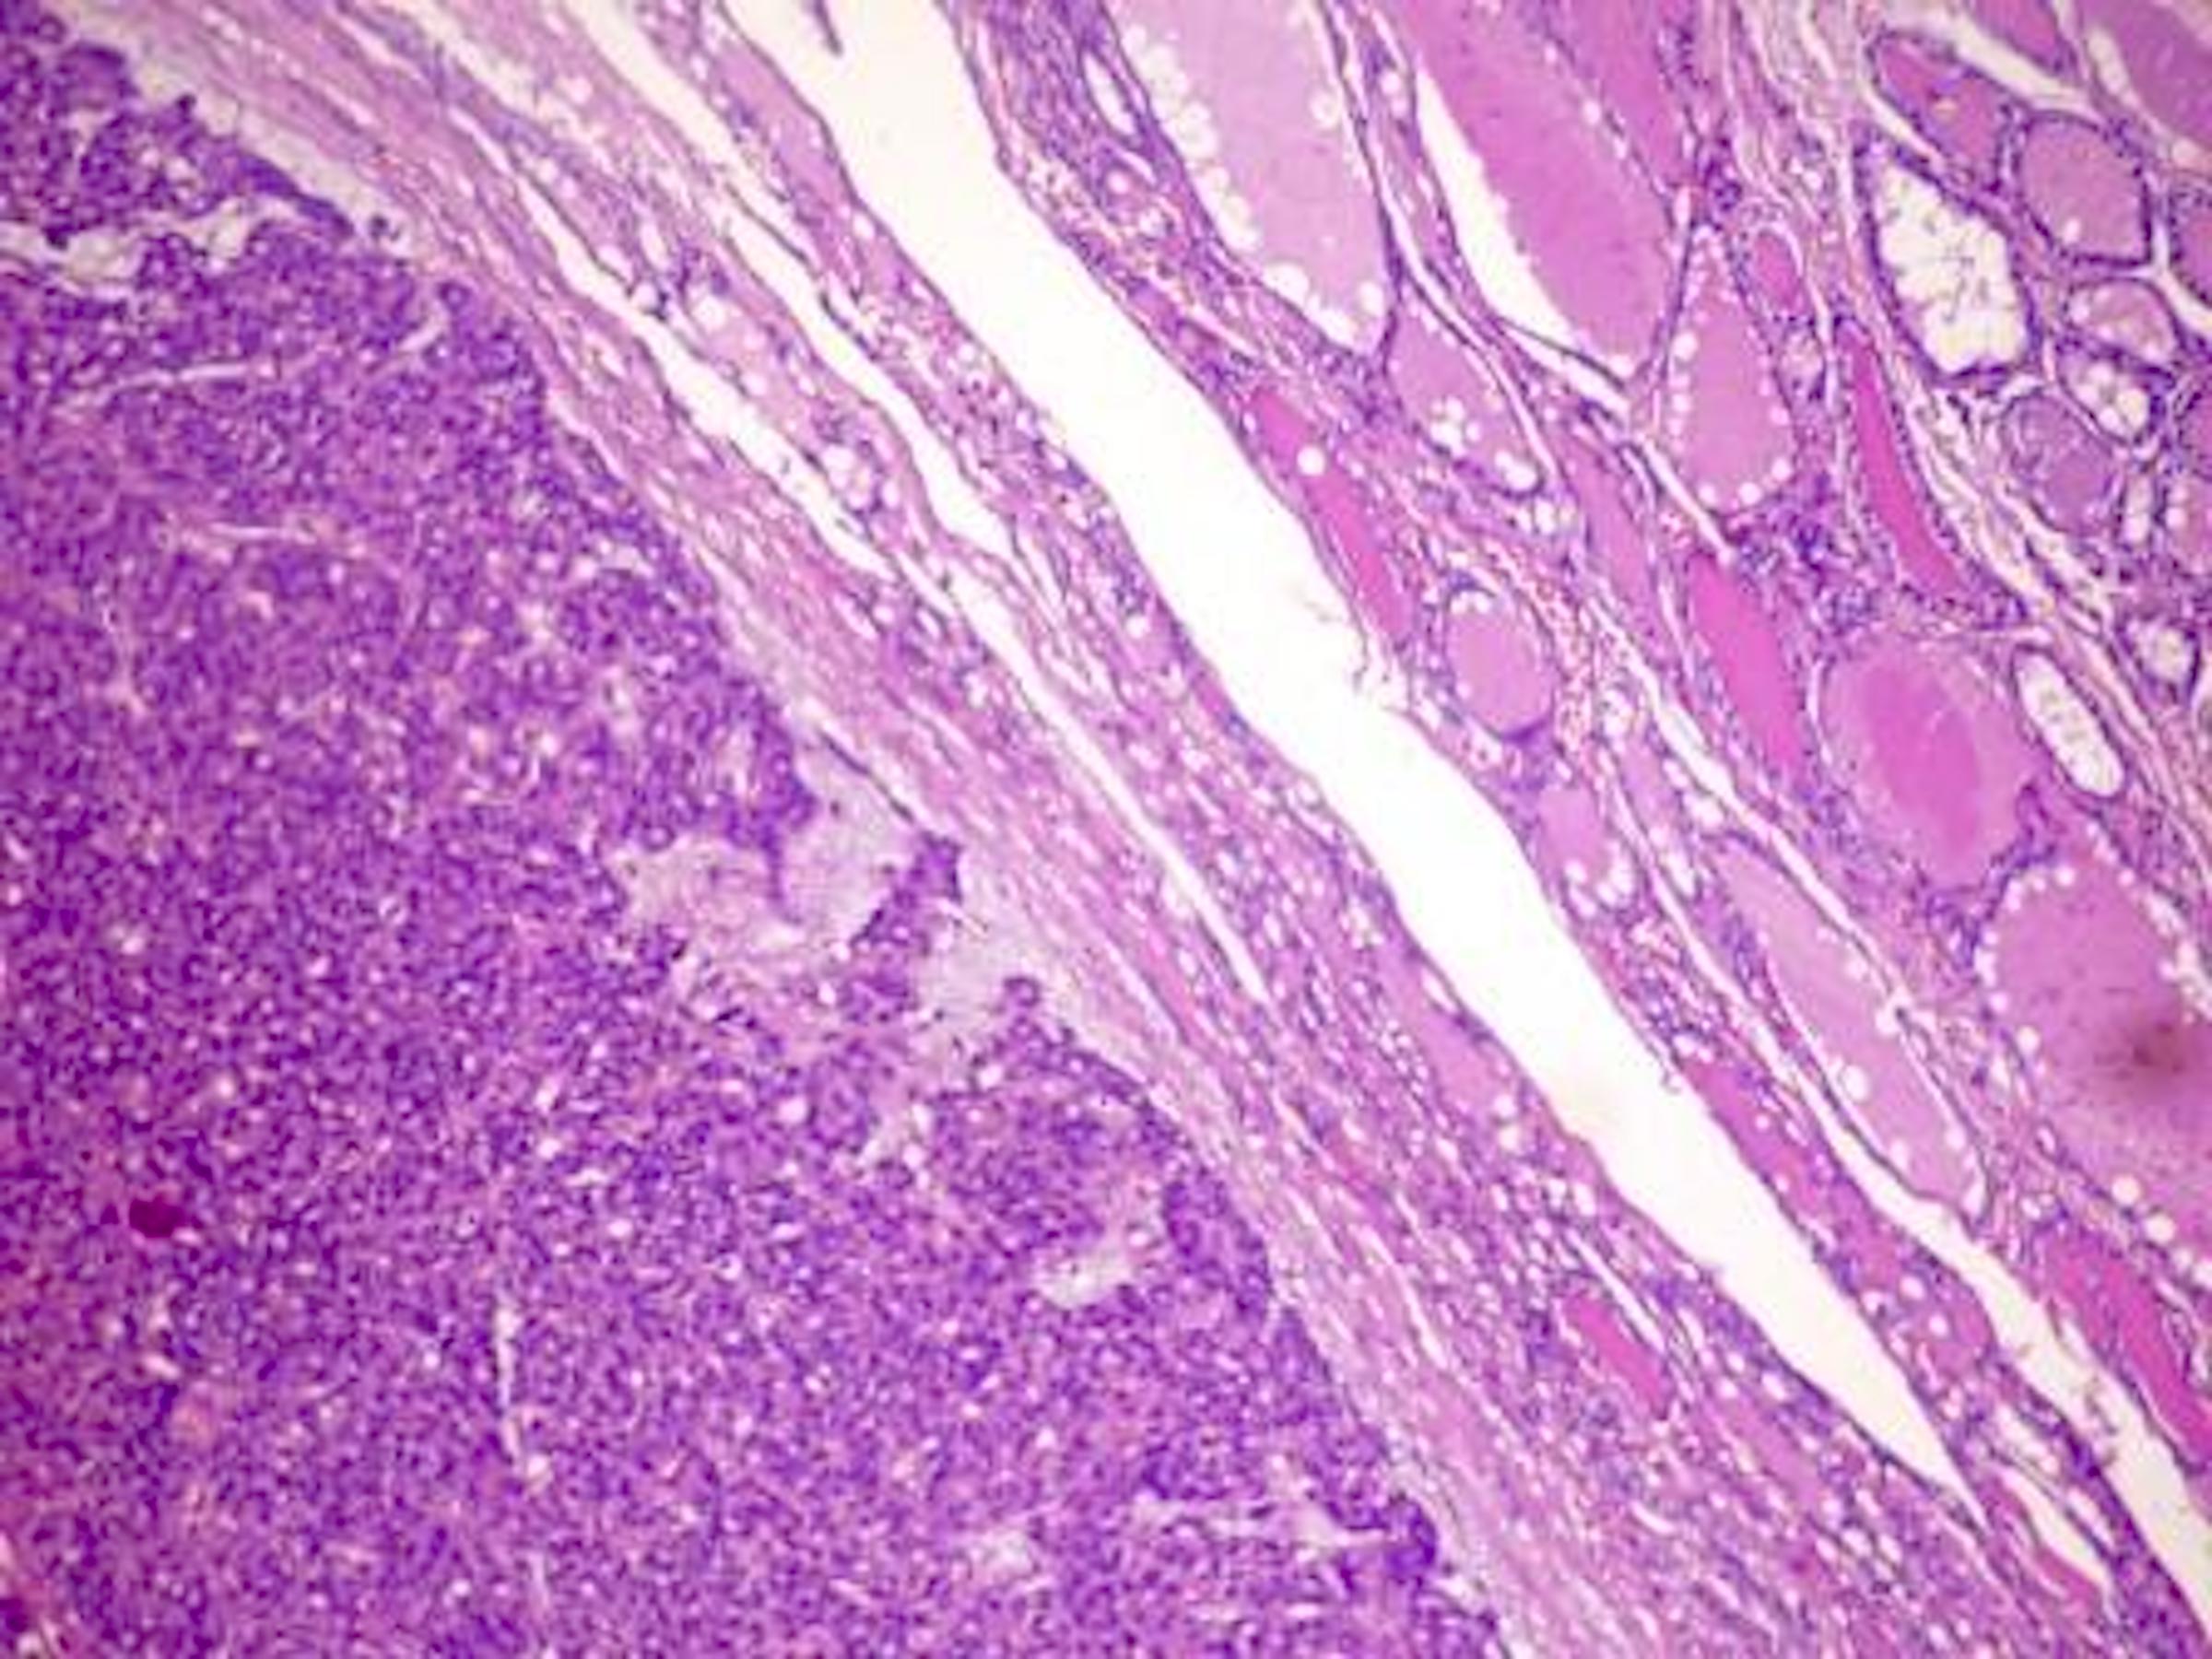

Microscopic (histologic) description

- Architecturally and cytologically different from surrounding gland

- Compression signs in surrounding thyroid tissue

- Encapsulated; thin or moderately thick capsule

- No capsular or vascular invasion after thorough sampling (at least 10 blocks)

Microscopic (histologic) images

Contributed by Shipra Agarwal, M.D., Andrey Bychkov, M.D., Ph.D., Mark R. Wick, M.D., Asmaa Gaber Abdou, M.D. and AFIP

Atypical adenomas:

Not invasion:

Differential diagnosis

- Nodular hyperplasia with dominant nodule:

- Hyperplastic changes elsewhere in gland

- Often not encapsulated or incomplete capsule of variable thickness

- Variable architectural patterns

- May be multiple; lack of compression signs in adjacent thyroid gland

- Minimally invasive follicular thyroid carcinoma:

- Thick capsule

- Vascular or capsular invasion

- May show increased mitotic activity; may have foci of necrosis